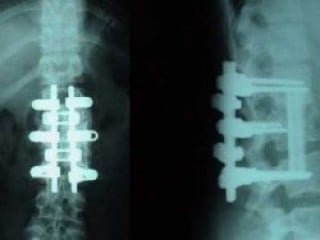

Halk arasında genellikle "platin" olarak anılan, kemik ve iskelet sistemini desteklemek için kullanılan mekanik malzemeler daha çok 316L çelik, titanyum, vitalyum veya krom kobaltlı bileşiklerden oluşuyor.

'Aslında insan vücudundaki destek malzemelerinin yapımında çoğunlukla 316L çelik, titanyum, vitalyum ya da bunların bazı bileşikleri olan krom kobaltlı bileşikler kullanmaktayız. Bir alaşımın kullanılmasında bizim için en önemli şey, vücut tarafından kullanılmasında hücrelerin bundan olumsuz etkilenmemesi yani zehirlenmemesidir. Bunun yanında canlılıklarını devam ettirebilmeleri, onun verdiği mekanik destekten mutlu olmaları o malzemenin esnekliğinin vücudunkine daha yakın bir malzeme olması ve hacim olarak az yer tutması da destek malzemelerinde dikkat edilen diğer bazı noktalardır.'

Doç. Dr. Alper Gökçe, günümüzde insan vücudunda en çok tercih edilen destek malzemesinin ise daha çok titanyum malzemesi olduğunu söyledi.

Vatandaşların platin yanılgısına kapılmalarında belki parlaklık, şekil ya da maddi sebeplerin etken olabileceğine vurgu yapan Gökçe, 'Ancak günümüzde platin yerine en çok titanyum malzemesi tercih edilir. Bu yönde bir yoğunlaşma vardır' diye konuştu.

'Biyolojik ortamda platinin çok yaygın bir kullanım alanı yoktur. Alternatif olarak daha iyi daha biyouyumlu malzemeler var. O yüzden platinin hemen hemen kullanımı yok denecek kadar azdır. Vücutta iki çeşit malzeme kullanırız. Biri geçici tespit materyalleri yani kırığınız olduğunda kemik iyileşinceye kadar iki kemik parçasını bir arada tutucu geçici materyaller. Bunları omurgada, kolda, bacakta, dizde, uzun kemiklerde kullanıyoruz.

İkinci materyaller ise protezler yani vücudun oynaklarında, oynak yüzeylerinin pürüzlendiği, bozulduğu, kireç biriktiği durumlarda pürüzsüz bir şekilde hareketi sağlamak için kullandığımız malzemelerdir. Bunlar seramik veya polietilen gibi plastik benzeri bir malzeme olabiliyor ya da daha çizilmez malzemeler olabiliyor. Bu materyallerin yapımında platin uyumlu olmuyor. Daha çok diğer alternatifleri kullanıyoruz.'